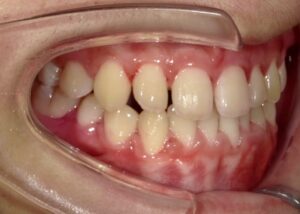

側面

- After